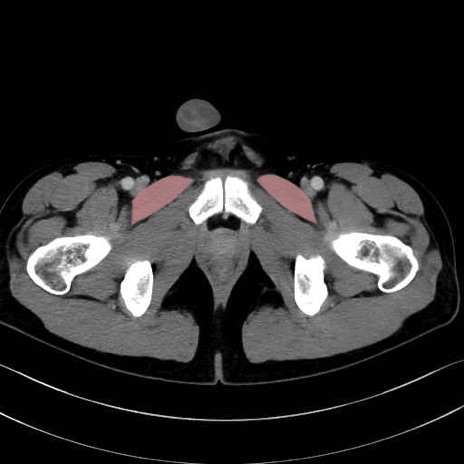

恥骨筋 (Pectineus)